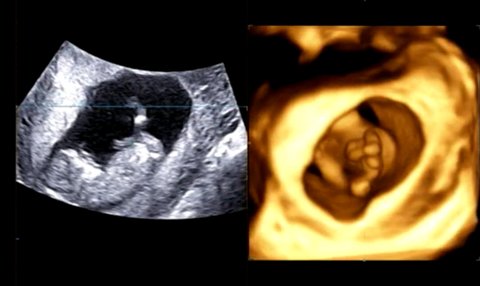

애기 성별구별좀 해주세요!!

괌가기전에 성별을 알아보구 애기옷사려고하는데

핑쿠일까요 블루일까요!?